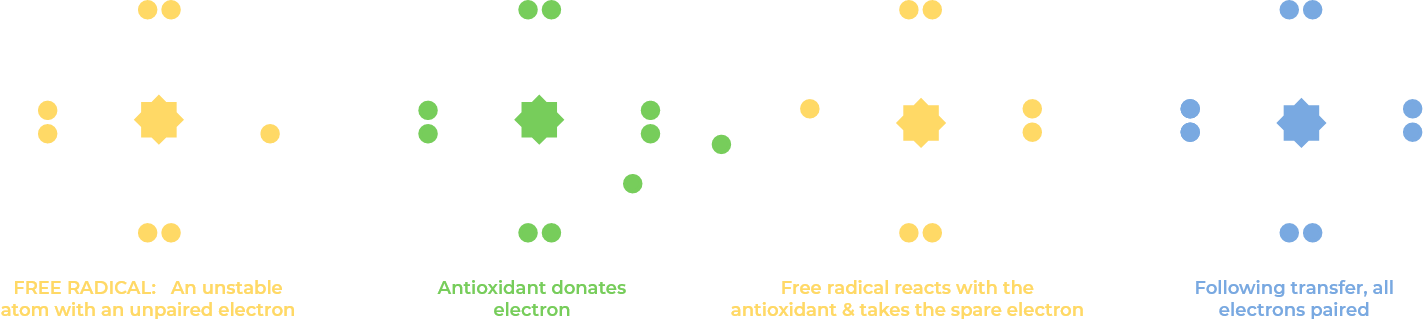

A free radical is any molecular species that has an unpaired electron and is thus highly unstable and reactive.

By either contributing or accepting an electron, they can behave as oxidants or reductants, respectively.

ROS, are oxidants. They are a group of unstable, oxygen-containing molecules that are chemically reactive due to the presence of unpaired electrons, and are a natural part of biological metabolism. They are a byproduct of normal cellular metabolism and play important roles in cellular signaling and other biological processes.

ROS can also be produced in response to environmental stressors such as pollutants and radiation. Pollutants cause damage by creating excessive ROS in the human body. This overwhelms the body's antioxidant defence creating an imbalance as the number of Oxidants exceeds that of anti oxidants.

When present in excess, ROS can damage cells by oxidizing essential biomolecules like proteins, lipids, and nuclei Cellular senescence or even Cell Death.